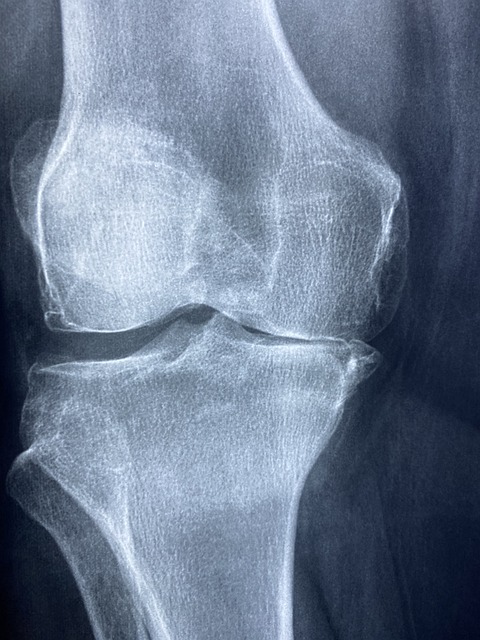

- 관절 통증 감소: 콘드로이친 효능으로 퇴행성 관절염 환자에게서 관절 통증을 줄이는 데 도움 됨이 있습니다. 이는 콘드로이친이 연골의 마모를 방지하고 염증을 줄이는 역할을 하기 때문입니다.

- 연골 보호 및 재생: 콘드로이친은 연골 세포의 생성을 촉진하고, 기존 연골을 보호하는 데 중요한 역할을 합니다. 이는 특히 나이가 들면서 발생하는 연골 손상을 예방하는 데 유용합니다.

- 염증 감소: 연구에 따르면 콘드로이친은 관절 내 염증을 감소시키는 데 효과적입니다. 이는 장기적으로 관절 건강을 유지하는 데 도움이 됩니다.

- 관절 유연성 향상: 콘드로이친 효능으로 정기적인 콘드로이친 복용은 관절의 유연성을 개선하고, 일상 활동의 질을 높이는 데 기여합니다.

여러 연구에서 콘드로이친의 효능이 입증되었습니다. 예를 들어, 골관절염 환자를 대상으로 한 연구에서 콘드로이친이 관절 통증을 감소시키고, 연골 손상을 방지하는 효과가 있는 것으로 나타났습니다. 이러한 연구들은 콘드로이친의 장기적 사용이 안전하고 효과적임을 시사합니다.